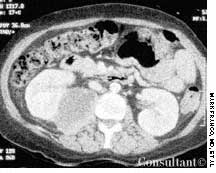

Police brought a delirious, combative 24-year-old man to the emergency department. The patient was unable to provide any history on arrival, but his scarred, blistering lips and his vital signs (blood pressure, 166/102 mm Hg; heart rate, 97 beats per minute; respiratory rate, 24 breaths per minute; and temperature, 38.2°C, or 100.9°F) led to a possible diagnosis of cocaine-induced delirium.